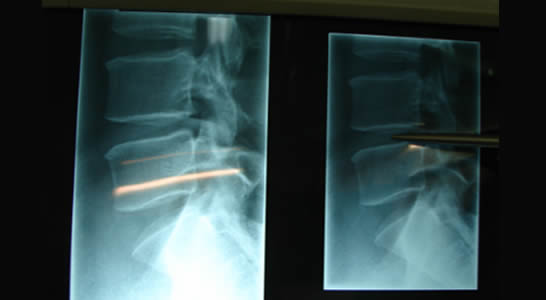

Paciente masculino de 45ª de edad con diagnóstico de Radiculopatia compresiva con disminución del espacio interdiscal L4 – L5, más hernia discal.

Se realizó procedimiento quirúrgico de columna a nivel de L4- L5 colocando el espaciador interespinosonúmero 14mm con resistencia de 100N

PREOPERATORIO:

TRANSOPERATORIO: